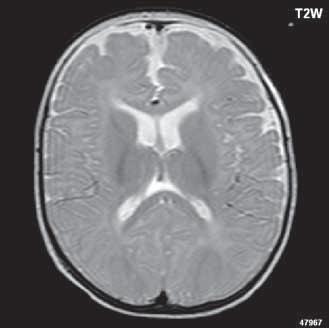

Obr. I.1.1f Rozšířené subarachnoidální prostory (věk 6 měsíců – v tomto období se nejedná o patologický stav, ale jsou fyziologicky prostornější)

Obr. I.1.1g Rozšířené subarachnoidální prostory (věk 6 měsíců – v tomto období se nejedná o patologický stav, ale jsou fyziologicky prostornější); stejný pacient jako na obr I 1 1f

f g h ch

Obr. I.1.1h Fyziologický nález, již normální šíře subarachnoidálních prostor (věk 1,5 roku); stejný pacient jako na obr I 1 1f, g

Obr. I.1.1ch Fyziologický nález, již normální šíře subarachnoidálních prostor (věk 1,5 roku); stejný pacient jako na obr I 1 1f, g, h